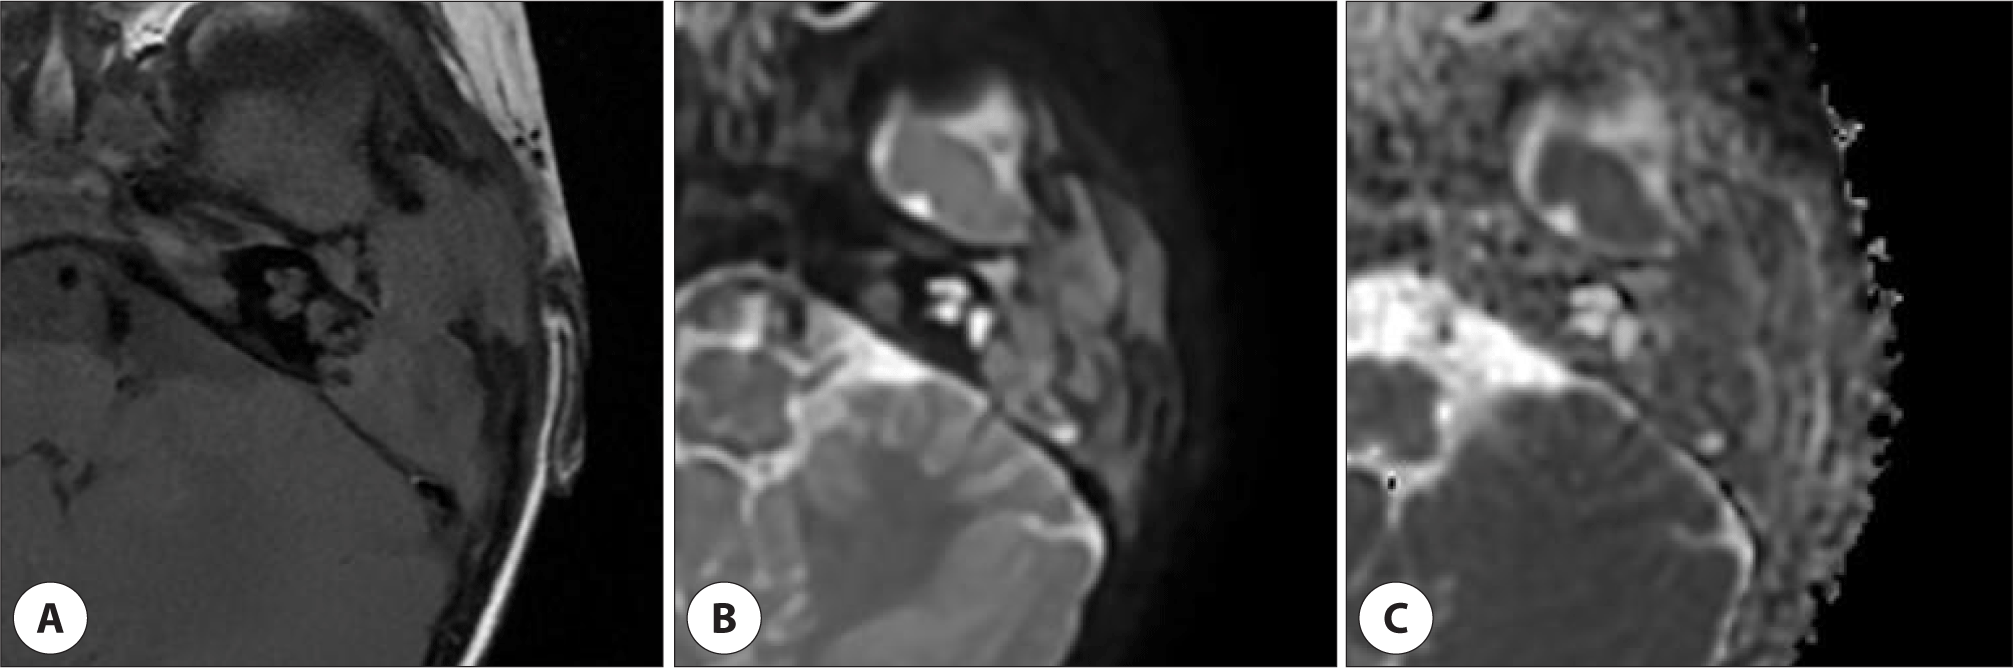

그러나 2개월 후 외이도 후방에서 종물이 돌출되는 양상으로 외이도 협착이 관찰되었고(Fig. 1B), 청성뇌간유발반응검사상 우측 30 dBnHL, 좌측 70 dBnHL로 좌측 난청 소견을 보였다. 정밀한 검사를 위해 측두골 전산화단층촬영(computed tomography, CT)을 시행하였다. CT에서는 좌측 유양돌기(mastoid), 측두골 인부(squamous part), 측두하악관절(temporomandibular Joint, TMJ)의 전방 및 상부, 외측 반고리관(lateral semicircular canal) 누공을 포함하는 광범위한 골 파괴성 병변이 확인되었으며, 중이강(middle ear cavity)에도 병변 침범이 확인되었으나 이소골의 파괴 소견은 명확하지 않았다(Fig. 2). 이후 확산 강조 자기공명영상(diffusion-weighted MRI[magnetic resonance imaging])에서는 동일 부위에 확산 제한 소견(diffusion restriction)을 동반한 병변이 관찰되어 진주종을 의심하였다(Fig. 3).

영상검사에서 LCH는 일반적으로 골 파괴와 연조직 종괴를 동반하는 소견을 보인다.3) 27명의 소아 환자를 대상으로 한 연구에 따르면, CT 상 유양돌기 내 경계가 명확한 용해성 골 병변과 연조직 음영이 흔히 관찰되며, 이소골은 대부분 보존되고 약 18%에서만 내이 미로낭 침범이 동반되었다.7) 본 증례에서도 이소골은 보존되었고, 외측 반고리관 일부를 제외하면 골성 미로 또한 보존된 상태였다. 이는 진주종에서 이소골 침범이 매우 흔한 점과 비교할 때, 감별 진단에 참고할 수 있는 소견으로 생각된다. 조영증강 MRI가 시행되었다면, 진주종은 일반적으로 조영증강을 보이지 않는 반면, LCH는 연부조직 병변에 조영증강이 나타나는 경향이 있어 감별 진단에 도움이 되었을 것이나, 본 증례에서는 술 전에 T1-weighted 및 diffusion-weighted MRI만 시행되었다. LCH 환자의 확산강조 MRI 소견에 대한 증례 보고는 아직 많지 않으나, LCH는 세포간 기질이 적고 세포 밀도가 높아 확산 제한을 보일 수 있는 병변이다. 본 증례에서도 확산 제한을 동반한 골 파괴성 병변이 관찰되어 초기에는 진주종에 의한 병변으로 의심하였으나, 이후 수술 및 조직검사를 통해 LCH로 확진되었다.